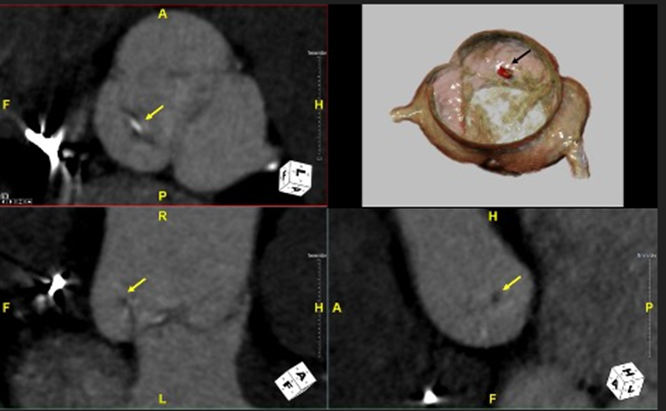

On the current presentation, the patient underwent repeat transthoracic echocardiography with bubble study and contrast-enhanced transthoracic echocardiography, neither of which demonstrated an intracardiac shunt or left ventricular thrombus. Electrocardiographically (ECG) synchronized cardiac computed tomography angiography (cCTA) was then performed as the final diagnostic test, supported by recent evidence demonstrating a higher diagnostic yield than echocardiography in the evaluation of acute stroke (Rinkel et al., 2022). cCTA revealed a 2-mm low-density tissue excrescence arising from the noncoronary cusp of the aortic valve (Figure 1) and simultaneously confirmed the absence of intracardiac thrombus or patent foramen ovale. Guided by cCTA localization, a repeat TEE with three-dimensional (3D) multiplanar reconstruction (Figure 2) successfully visualized the lesion. Intraoperative four-dimensional (4D) TEE with CT fusion—an innovative multimodality integration not previously described for this indication—was subsequently used for precise leaflet localization (Figures 3 and 4). Surgical pathology (Figure 5) demonstrated fibrocalcific degenerative changes of the noncoronary cusp and a small papillary fibroelastoma (PFE), which was deemed the most likely source of the patient’s recurrent cerebrovascular events.

Figure-1